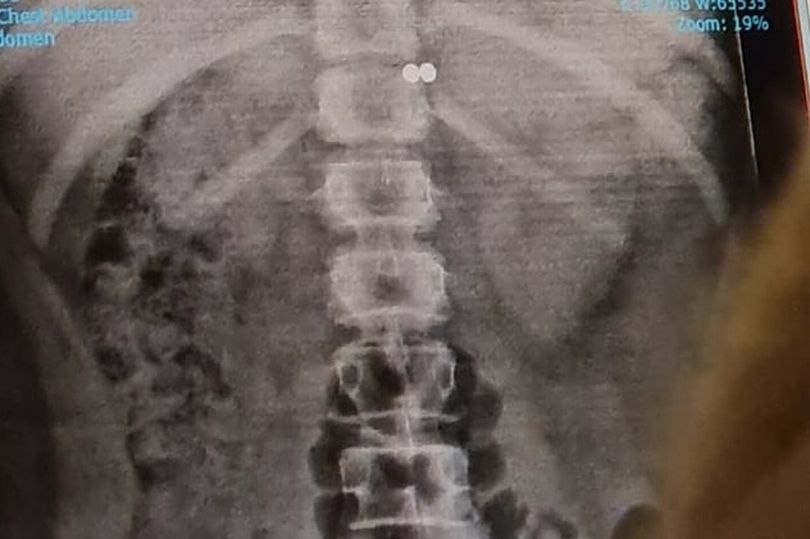

Теперь появился новый повод для родительской паранойи. Ведь в TikTok завирусился опасный тренд. Так 12-летняя девочка хотела изобразить "пирсинг" с помощью двух магнитных шариков. Вот только координации не хватило — и ребёнок случайно проглотил шарики. Ребёнка пришлось везти в больницу.

Достать магниты без хирургического вмешательства так и не получилось. Теперь девочку ждёт не только операция, но и кое-что пострашнее